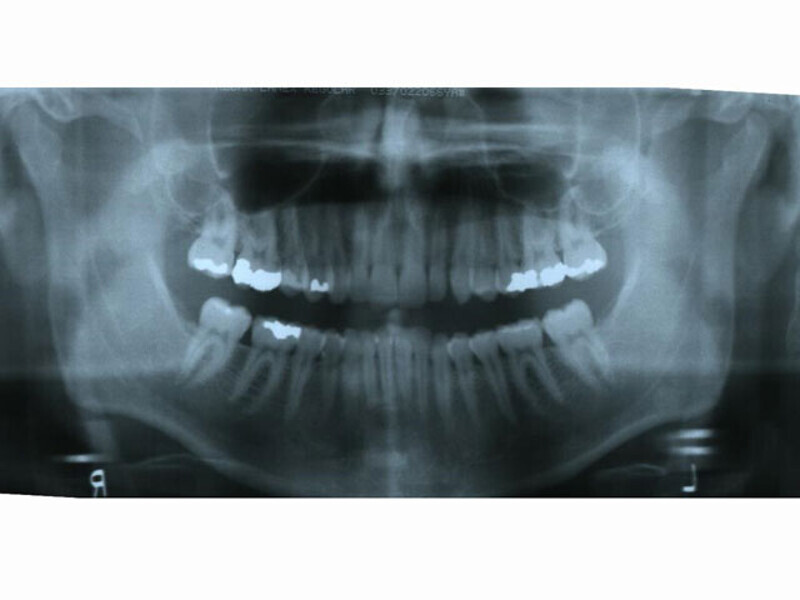

ClearCorrect treatment of crowding